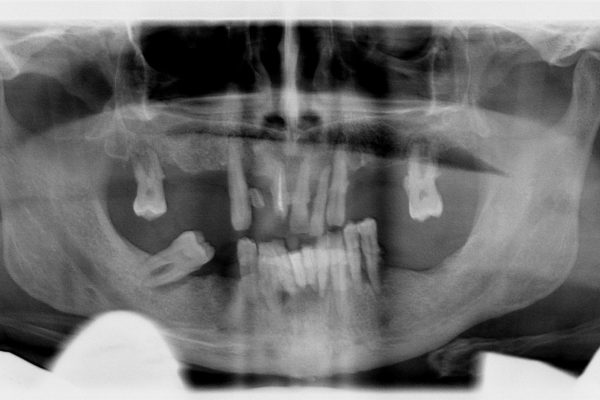

Anche in casi estremamente complessi, la riabilitazione Implanto-protresica , se ben pianificata, può dare dei risultati soddisfacenti, sia dal punto di vista estetico che funzionale.Scopri di più